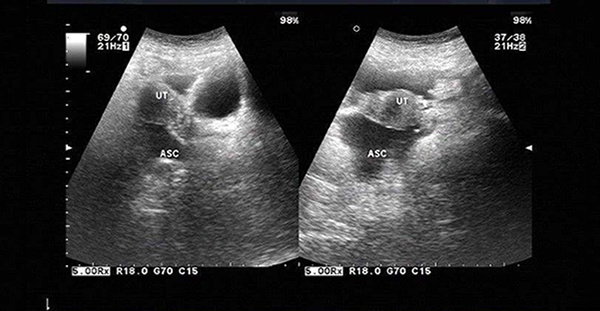

B超检查下的盆腔积液

盆腔积液分为生理性盆腔积液和病理性盆腔积液两种,而生理性盆腔积液常发生于女性的月经期或排卵期,而盆腔积液4.9已经属于病理性盆腔积液,若不及时治疗,会影响到胚胎移植。

对于取卵后盆腔积液不正常的女性来说,需要先诊断病因和病情,盆腔积液的位置多发生在子宫直肠陷凹等盆腔内位置较低处,妇科常用的有效检查手段是B超,可以较准确的判断积液的量,然后再治疗。